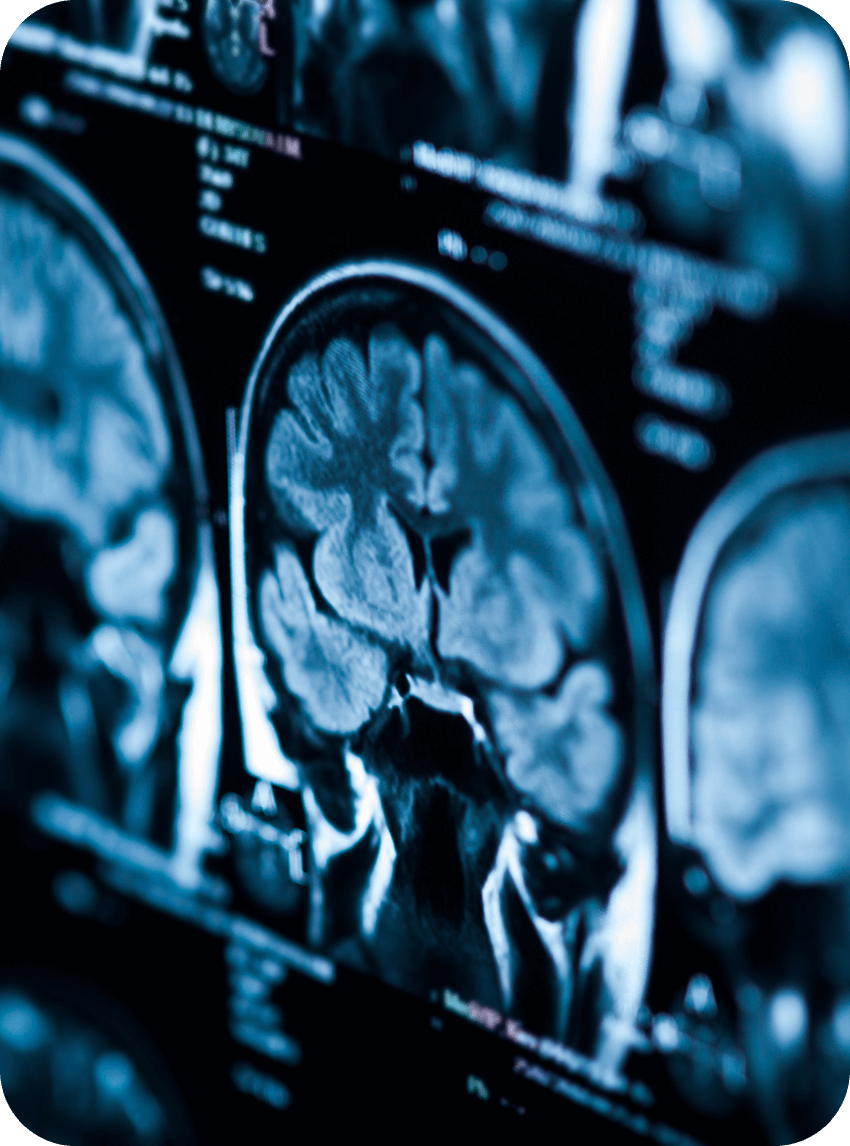

Expert evaluation and treatment of brain, spinal cord, and nervous system conditions following auto accidents and personal injury cases.

Neurology at Total Injury Care focuses on evaluating and treating conditions that affect the brain, spinal cord, and nervous system following traumatic incidents. Our neurology providers take a patient-specific approach to identify the underlying causes of complex symptoms.

Neurology is a critical part of recovery after an auto accident, identifying and addressing conditions that may affect sensation, movement, cognition, and overall function, helping patients return to daily life safely.

Identifying traumatic brain injuries, peripheral nerve damage, and spinal cord complications through expert testing.